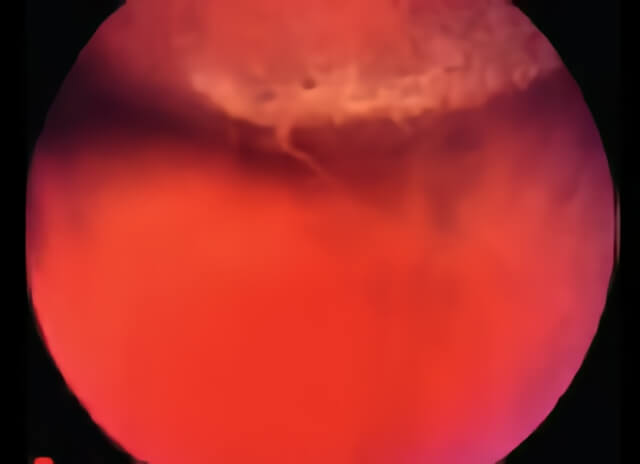

In this photo, the surgeon is gently pressing in on the eye in order to enhance the view of the small hole within an area of lattice degeneration.